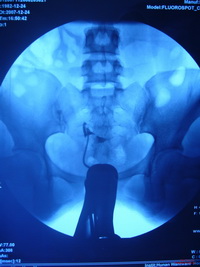

二、子宮輸卵管碘油造影術(HSG)

子宮輸卵管碘油造影術操作簡單,可在螢屏下直視子宮及輸卵管內部結構和形態。其優點是:1、診斷迅速,準確,術中即可判定子宮原因或輸卵管原因,部位確切。有研究表明,HSG判斷梗阻部位優於腹腔鏡。2、可在直視下適當加大壓力,以分離輕度宮腔粘連。3、安全,因在直視下操作,可發現術中意外情況,如碘化油進人血管、淋巴,及時停止注藥,以防油栓發生引起不良後果。但其所用造影劑(如碘油)不良反應大,易刺激黏膜引起過敏,且油性造影劑粘稠,難以通過輸卵管狹窄部,判斷梗塞部位較困難。